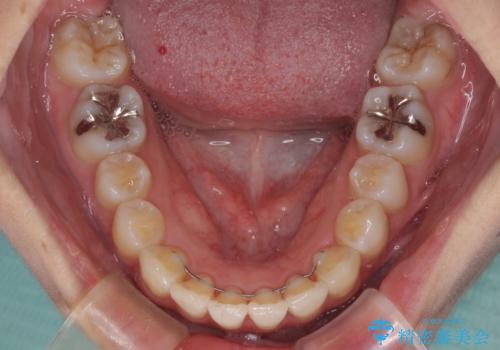

歯列全体の拡大と、歯と歯の間を削ることでスペースを獲得し、インビザラインによる矯正治療を行うこととしました。

骨格的な問題を抱えた左奥以外は比較的早く咬み合わせが改善しましたが、左奥はどこで咬み合えば良いのか分からず、大変不便な思いをされていました。

ゴムかけにご協力いただき、最終的には反対咬合を改善することができ、患者様には大変満足していただきました。